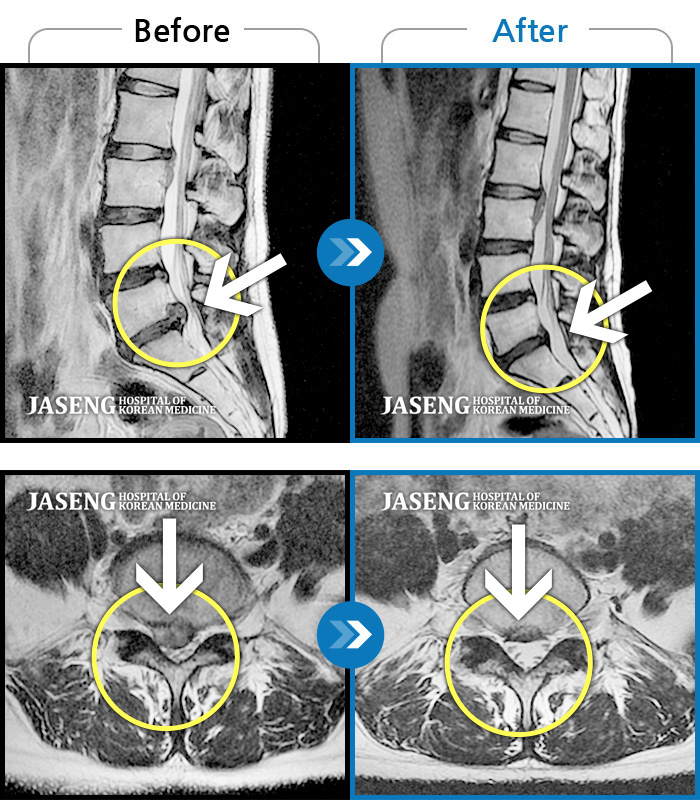

MRI 치료사례

극심한 허리와 좌측 하지 방사통 및 마비감으로 모든 자세가 힘들었다.